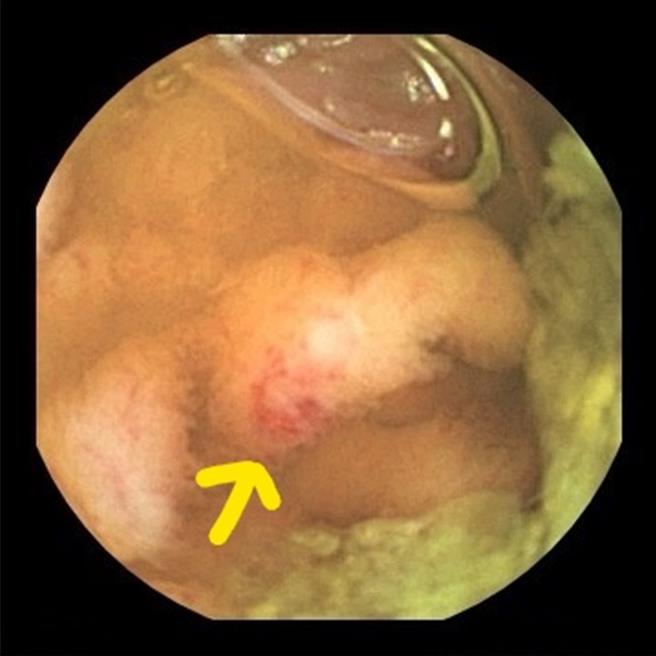

箭頭所指處即為出血處。(院方提供/李京昇台中傳真)

胡書瑋說,從內視鏡檢查影像中判讀發現,小腸有許多潰瘍以及出血的痕跡,研判男童罹患克隆氏症早期,用藥治療後,出血止住並控制病情,男童也順利出院,持續門診追蹤治療。